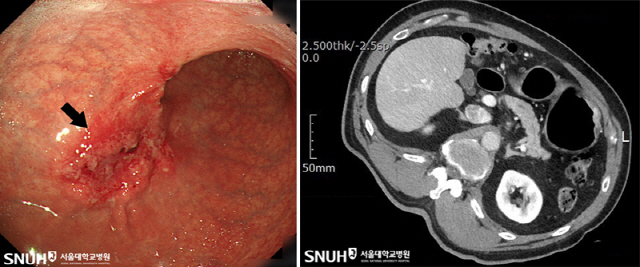

가장 중요한 진단 방법은 위내시경 검사다. 위장조영술도 가능하지만 이는 아주 초기의 위암을 발견하기는 어렵다. 따라서 위내시경을 통해 직접 눈으로 확인하는 것이 효과적인 진단 방법이며, 병변이 있을 경우 조직 검사를 통해 확진할 수 있다.